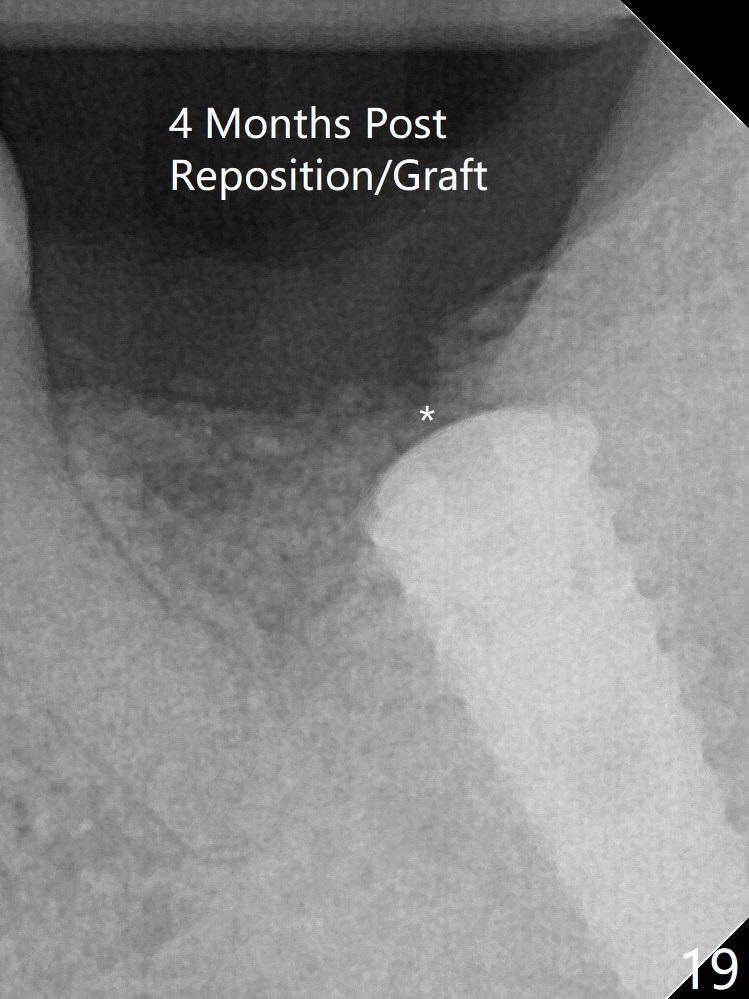

术后四个月伤口愈合,骨粉几乎没有丢失(图十九:*)。切开,刮匙去骨,有一定硬度,即刻放置修复基台,完全就位(图二十),制备临时牙冠,牙周敷料固定组织瓣(没有缝线)。术前